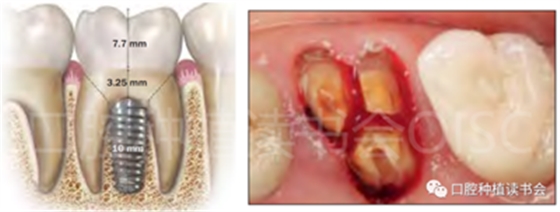

Smith和Tarnow根據(jù)種植體在拔牙窩內(nèi)獲得初始穩(wěn)定性的情況提出了一個(gè)后牙位點(diǎn)即刻種植的分類系統(tǒng)。分為A型、B型和C型三種(圖4)。

圖4 Smith和Tarnow后牙位點(diǎn)即刻種植分類。

3.1 A型拔牙窩:

A型拔牙窩,種植體可完全放置在間隔骨內(nèi),在種植體和拔牙窩骨壁之間無(wú)空隙(圖5),可按照理想的三維位置在牙槽間隔內(nèi)進(jìn)行種植體的植入。

圖5 A型拔牙窩-種植體植入到牙槽間隔內(nèi),并被骨完全包繞。

如果不進(jìn)行即刻修復(fù),初期穩(wěn)定性大于15Ncm通常就可以獲得成功骨結(jié)合,研究報(bào)道成功率大于86%,如果初始穩(wěn)定性大于30Ncm,則骨結(jié)合的成功率大于90%【Akimoto等.1999】。

3.2 B型拔牙窩:

B型拔牙窩,有足夠的間隔骨來(lái)穩(wěn)定種植體,但不能完全包圍,在種植體的一個(gè)或多個(gè)表面和拔牙窩骨壁之間留有間隙(圖6)。